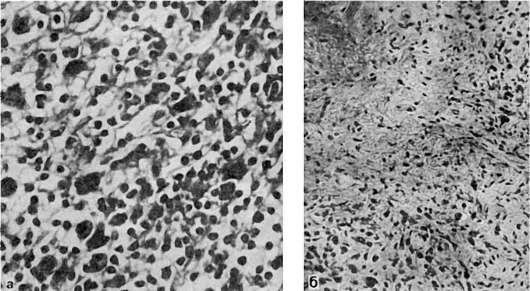

Рис.

138. Африканская лимфома (опухоль Беркитта):

а - локализация опухоли в верхней челюсти; б - гистологическая картина опухоли - «звездное небо» (препарат Г.В. Савельева)